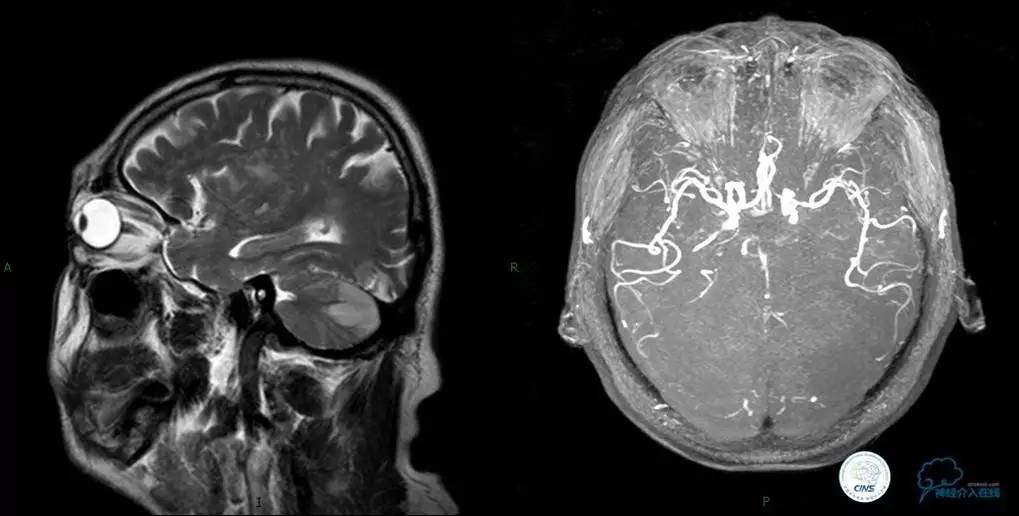

▼头颅MR

▼入院MR